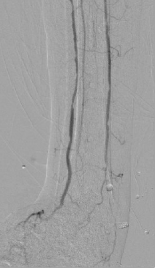

多年来,贵州航天医院各科室紧跟医学前沿,不断强技术、补短板,大力开展新技术、新项目,完成了许多高精尖、高难度、本地区“首例”的技术,填补了医院医疗技术空白,满足了群众日益增长的医疗需求。 贵州航天医院骨科率先在遵义地区开展骨搬移技术,截至目前,已治愈慢性骨髓炎、感染性骨不连、骨缺损、脉管炎、糖尿病足患者200余例,糖尿病足治疗保肢率达到98%。 本期,我们将为大家带来骨科特色技术——骨搬移技术(Ilizarov)。 案例分享 一名59岁的患者,身患糖尿病12年,在来我院3个月前出现了右脚溃烂的症状,来院就诊时,患者的右脚十分红肿,右脚脚趾坏死,伤口处不断流出黑红色脓液,情况十分严重。在接诊到患者时,骨科专家团队高度重视,立刻为患者完善了CT血管造影(CTA)等相关检查,诊断为:2型糖尿病,糖尿病周围血管病变,右糖尿病足。 术 前 考虑到患者情况比较严重,为最大限度保证患者肢体完整,科室专家团队进行了严格的讨论评估,为患者制定了骨搬移技术治疗方案,在征得患者及其家属的同意后,成功通过搬移骨块为患者进行治疗,促进患者病变肢体血管再生。 胫骨横向骨搬移外架固定 清除感染病灶 术后调节外架,通过搬移骨块 促进患肢血管再生 患者在术后三周前来换药,观察到感染得到进一步控制;术后六周复查,患者病变处已愈合,进行CT血管造影(CTA)后可明显观察到足部血管再生。 术后3周 术后6周愈合 CT血管造影见足部血管再生 糖尿病患者全身与局部的问题互为影响,形成恶性循环,糖尿病足溃疡创面迁延不愈,常见干性坏疽、湿性坏疽、趾坏死、深且大的溃疡以及骨髓炎等症状,还可导致脓毒血症,以往为保全生命,患者被迫选择一次或多次截肢。骨搬移技术的发展进步,能在血糖有效控制、局部有效清创下,有效促进患肢微血管再生,改善患肢血供,达到糖尿病足更快治疗康复的目的,并能根据病变情况最大限度的保障患者肢体完整。 什么是骨搬移技术 骨搬移技术是通过使用专用的骨外固定器固定骨段,每天缓慢牵拉,在牵拉搬移过程中,骨段尾部形成新骨及新的软组织,从而修复骨骼缺损及软组织缺损。是治疗大段骨缺损、骨不连、骨感染、肢体畸形的金标准方法,也用于治疗脉管炎、糖尿病足等肢体缺血性疾病。 骨感染缺损 切除感染段 搬移骨段 新骨形成 骨感染根治愈合 骨搬移技术原理 生物组织在持续、稳定、缓慢牵拉下,能刺激细胞分裂、组织再生,骨外固定技术运用该原理,通过持续缓慢调节外固定器形成牵拉张力,促进牵引成骨与相邻组织再生,如神经、血管、肌肉、皮肤等再生,达到治疗大段骨缺损、肢体缺血如糖尿病足等疾病的目的。 骨搬移技术优势 (一)除治疗骨缺损、骨不连外,有更广的适用范围,利用组织再生、血管再生等特性,能大量运用于肢体畸形的矫形、糖尿病足等的治疗。 (二)治疗效果确切,重建肢体外型和功能,极大降低截肢率和残疾率。 (三)明显提高了患者生活质量,极大减轻其家庭及社会负担。 肢体畸形的矫形 慢性骨髓炎 骨段切除 术后1年 濒临截肢的脉管炎术后6周 难愈创面术后3周 贵州航天医院骨科 专家团队 赵学平 骨科主任 主任医师 临床擅长:从事骨科临床工作30余年,对骨科常见疾病的诊治具有丰富的临床经验。 世界中医药联合会脊柱康复专业委员会常务理事,中华中医药学会整脊分会常务委员,中国中西医结合学会骨伤科分会肢体矫形功能重建与康复专家委员会常务委员,中国研究性医院学会骨科创新与转换专业委员会关节外科学组保髋工作委员会常委,中国康复技术转化及发展促进会骨外科与康复技术转化专业委员会常务委员,泛珠三角区域运动医学联盟(PPRD-SMA)理事会常务理事,中国研究型医院学会运动医学专业委员会委员,贵州省中医药学会整脊分会副主任委员,贵州省中西医结合学会银质针专业委员会副主任委员,贵州省康复医学会骨与关节专业委员会常务委员,贵州省人民医院骨科专科联盟常务理事,贵州省康复医学会骨内科专业委员会常务委员,中华医学会贵州省骨科学会委员,贵州省康复医学会脊柱脊髓专业委员会常务委员,贵州省运动医学分会委员,贵州省康复医学会骨与软组织肿瘤专业委员会委员,遵义市医学会创伤分会副主任委员,贵州省康复医学会骨内科专业委员会遵义地区分会常务委员,遵义市医疗事故鉴定、伤残鉴定、工伤鉴定、司法鉴定专家。 长期从事骨科临床研究及教学工作,在国家级、省部级杂志发表论文20余篇,SCI论文2篇,参与主编骨科专著2部,主持省部级科研项目2项,参与指导省部级、市级科研项目6项。 陈明勇 骨科副主任 副主任医师 临床擅长:从事创伤骨科工作约20年,对骨缺损、骨不连、骨肿瘤、肢体畸形等的肢体矫形重建及功能重建,慢性化脓性骨髓炎的根治治疗、糖尿病足的保肢治疗、快速康复理念(ERAS)下的老年骨折的诊治,四肢复杂骨折的诊治,四肢骨折等微创手术治疗具有丰富的临床经验。 2004年毕业于遵义医学院临床专业,曾在中国人民解放军总医院、广西医科大学第一附属医院、上海第六人民医院骨科进修。中国中西医结合学会骨伤科专业委员会横向骨搬移治疗糖尿病足及微血管网再生学组首届委员,遵义市医学会创伤分会常务委员。 瞿 辉 骨科 副主任医师 临床擅长:对骨科的常见病、关节外科、脊柱外科及运动医学疾病的诊治具有丰富的临床经验,熟练掌握骨科手术操作技术。 毕业于遵义医学院临床医学系,2005年前往广州中山大学第一附院骨显微医学部进修学习,2011年前往成都华西医院进修学习,并多次在省内外学习骨科相关知识,是中华医学会骨科分会会员。 赵兴东 骨科 主任医师 临床擅长:擅长骨科的常见病及各种创伤、四肢骨折创伤修复、骨感染、手足疾病的诊治和手足体表畸形的矫形整复,熟练掌握骨科四肢骨病及创伤的手术操作技术,尤其在四肢关节复杂性损伤、手足外伤、组织缺损创面、难治创面的皮瓣修复方面及平足、高弓足矫形方面及四肢慢性疼痛诊治、康复方面具有丰富的临床经验。 硕士研究生,毕业于遵义医学院临床外科系,2015年前往山东省立医院手足外科进修学习;遵义市医学分会创伤分会第一、二届委员,遵义市手外科医学会第二委届员会常务委员;在省级及省级以上期刊发表文章9篇,参编著作2部,参与主持并完成市级课题1项,参与市级课题2项、省级课题1项。 张俊凯 骨科 副主任医师 临床擅长:从事骨科临床工作28年,对创伤骨折、骨感染、骨缺损、骨不连等外科诊治,四肢骨折的微创手术治疗,四肢复杂骨折(如关节内粉碎性骨折、多发骨折等)的损伤控制及手术治疗等具有丰富的临床经验。 1995年毕业于遵义医学院临床专业,2009年前往复旦大学附属医院骨科进修1年。 卢懿明 骨科 副主任医师 临床擅长:从事骨科工作18年,对创伤骨折、四肢骨折的微创手术治疗、四肢复杂骨折(如关节内粉碎性骨折、多发骨折等)的损伤控制及手术治疗,尤其是髋部骨折的PFNA等微创技术,踝关节骨折、膝关节周围骨折的Mipo微创技术等具有丰富的临床经验,开展了4项新技术,发明6项新型专利技术。 2005年毕业于遵义医学院临床专业,2017年,前往南方医科大学第三附属医院骨科进修半年,回院后运用Mipo技术对骨干骨折及干骺端骨折的治疗技术,同时积极开展骨盆骨折、髋臼骨折腹直肌外侧切口的应用;发表了多篇专业论文,经常参与省内外学术交流会授课,获得医院荣誉称号多个。 邬夏荣 骨科 副主任医师 临床擅长:从事骨科工作16年,对四肢复杂骨折、骨肿瘤的诊治,尤其是足踝创伤、慢性踝关节损伤、平足症等诊疗具有丰富的临床经验。 2006年毕业于遵义医科大学临床医学专业,曾在陆军军医大学西南医院进修学习,发表多篇骨科学术论文。 余德怀 骨科 副主任医师 临床擅长:从事骨科工作10余年,对运动医学、骨关节、脊柱外科常见病、多发病的诊治具有丰富的临床经验。 硕士研究生,2011年毕业于遵义医学院临床医学专业,曾前往遵义医科大学附属医院运动医学专业进修学习;是贵州省医学会运动医学分会青年委员,西部关节镜联盟委员;发表多篇骨科学术论文。 冯 乾 骨科 副主任医师 临床擅长:从事骨科工作近20年,熟练掌握骨科多发病及常见病的诊治,尤其对脊柱退变性疾病的诊断及治疗具有丰富的临床经验,主要研究脊柱微创相关治疗方式,能熟练开展椎间孔镜及VBE。 曾前往北京大学第三医院进修学习疼痛及椎间孔镜、首都医科大学友谊医院专业进修脊柱内镜;是贵州省康复医学会第三届脊柱脊髓专业委员会委员;发明专利3项、发表脊柱外科专业论文多篇。 张艳金 骨科 副主任医师 临床擅长:从事骨外科工作16年,对复合伤、多发伤的救治、四肢骨干骨折、关节周围骨折、骨肿瘤、骨髓炎等诊治具有丰富的临床经验。 中共党员,硕士研究生,2006年本科毕业于山西医科大学第二临床医学院,2011年研究生毕业于北京军区总医院;在“老年COPD患者合并髋部骨折的诊治”国际合作课题组研究两年,在老年髋部骨折的诊治方面具有丰富的经验,并发表论文6篇;承担遵义市级课题1项;承担遵义医科大学的临床教学工作,获得遵义医科大学优秀带教老师荣誉。编撰有《骨科疾病诊疗精粹》一书,开展2项新技术,编撰地方规范《务川自治县创伤骨科常见疾病诊疗规范》一书。 赵小锋 骨科 副主任医师 临床擅长:从事骨科临床工作11年,对骨科常见病、多发病诊疗有较为丰富的临床经验,擅长脊柱相关疾病诊断及治疗,尤其是颈、腰、腿疼痛疾病诊断及治疗,擅长胸腰椎骨折微创经皮穿刺内固定术、经皮穿刺椎体成形术、经皮穿刺脊柱内镜下腰椎间盘摘除术、单纯开创腰椎间盘摘除术、腰椎滑脱复位椎间植骨椎融合内固定术、腰椎管狭窄减压融合内固定术及人工髋、膝关节置换术等。 2012年毕业于遵义医学院外科学专业硕士研究生,2019年参加“遵义市115医学人才精英计划”于上海交通大学第一附属医院培训学习,2023年于北京大学第三人民医院脊柱外科进修学习,曾获得遵义市优秀医师荣誉称号。 遵义市手外科第一届委员,遵义市医学会创伤分会第一届委员,遵义市医学会创伤分会第二届委员,贵州省康复医学会第三届脊柱脊髓专业会委员,遵义市医学会烧伤与整形外科学分会委员,发表论文5篇,其中国家级核心期刊1篇,SCI论文1篇,主持市级课题1项并结题,参与市级课题2项。 贵州航天医院骨科简介 基本情况 贵州航天医院(原3417医院)骨科组建于1968年,前身是以创伤和断肢(断指)再植闻名于世的上海市第六人民医院骨科,中国断肢(断指)再植的奠基者、中科院院士陈仲伟等著名专家、学者多次莅临科室指导医疗、教,是贵州省最早拥有专业骨科技术科室之一,在70年代开展了贵州省首例断肢(断指)再植手术。组建50余年来,诊治患者已逾百万,挽救了无数的伤病员,成为了保障遵义地区人民群众健康的重要支撑。 经过几代人的不懈努力,今天的骨科,已由创伤骨科发展至骨病、骨肿瘤、骨结核等领域,现有脊柱外科、关节外科、四肢创伤、手足外科四个亚专科,成为了集医疗、教学、科研于一体的综合学科,是贵州省临床重点专科、遵义市临床重点专科、遵义市骨科临床医学中心、遵义市基层骨科专科联盟理事长单位。 科室目前开放床位110张,共有医护人员50余人,副高级以上专家18人,硕士研究生15人。拥有一流骨科医疗设备多台,每年不定期选派优秀技术骨干到全国各大知名医学院校进修、学习、参观、交流,并邀请国内、国外知名专家教授来院进行交流、指导,通过不断引进国内外先进的诊疗技术,科室医疗技术水平稳步提升,为广大人民群众提供了优质的医疗服务。 专科特色 骨一科 (一)骨缺损、骨不连的肢体与功能重建 胫骨横向骨搬移技术治疗糖尿病足: (二)慢性骨髓炎的根治治疗 (三)肢体缺血性疾病如糖尿病足、脉管炎的保肢治疗 (四)皮瓣修复 (五)复杂创伤的治疗 (六)老年髋部骨折及小儿骨折快速手术 老年髋部骨折: 骨二科 (一)胸腰椎骨折微创经皮椎弓根螺钉固定术 (二)老年性骨质疏松性患者腰椎滑脱脊柱内固定术(骨水泥螺钉) (三)V形双通道脊柱内镜技术(VBE)腰椎融合术治疗腰椎退行性疾病 (四)老年性骨质疏松性骨折(PVP/PKP)术 (五)人工髋关节置换术 (六)双侧股骨头坏死人工全髋关节置换 (七)右侧全髋置换术后假体周围骨折翻修 (八)人工膝关节置换术 (九)人工膝关节假体松动翻修 (十)关节镜技术 传统手术切口 关节镜技术切口 诊疗范围 骨一科 1.四肢创伤、矫形。 2.手、足踝外科。 骨二科